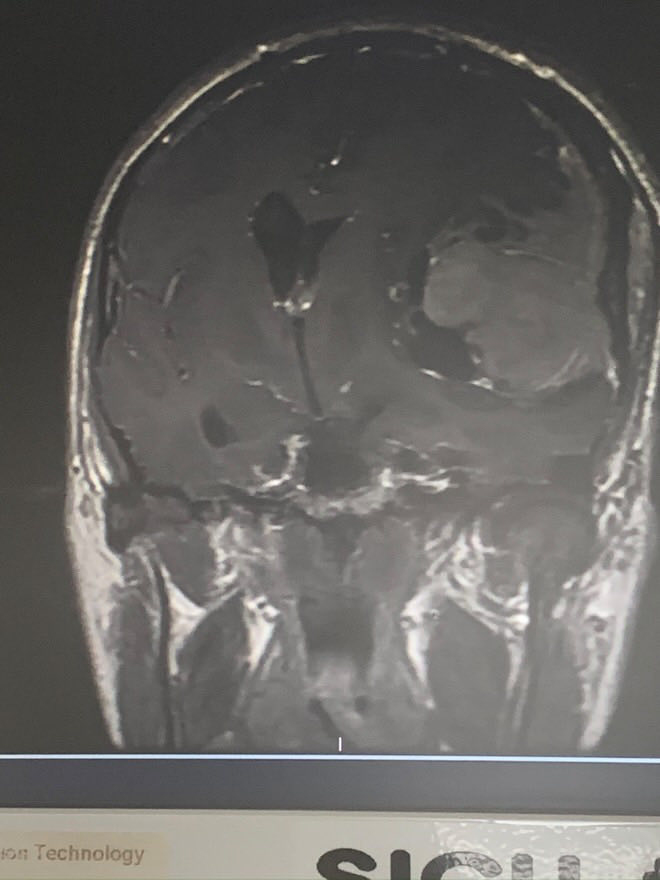

Emilijan je mesecima bio pod velikim stresom, a onda mu je 2019. na mozgu otkriven rak veličine šake.

-Počela je pandemija Covida a ja sam osetio da nešto nije u redu, imao sam glavobolje, padao u nesvest. Ispostavilo se da imam ogroman tumor u glavi, a operisao me jedini lekar koji ne hteo da me pregleda, Grk pravoslavac. Bog me je poslao nekome ko veruje u Boga i ja sam nekako znao da sam u pravim rukama.